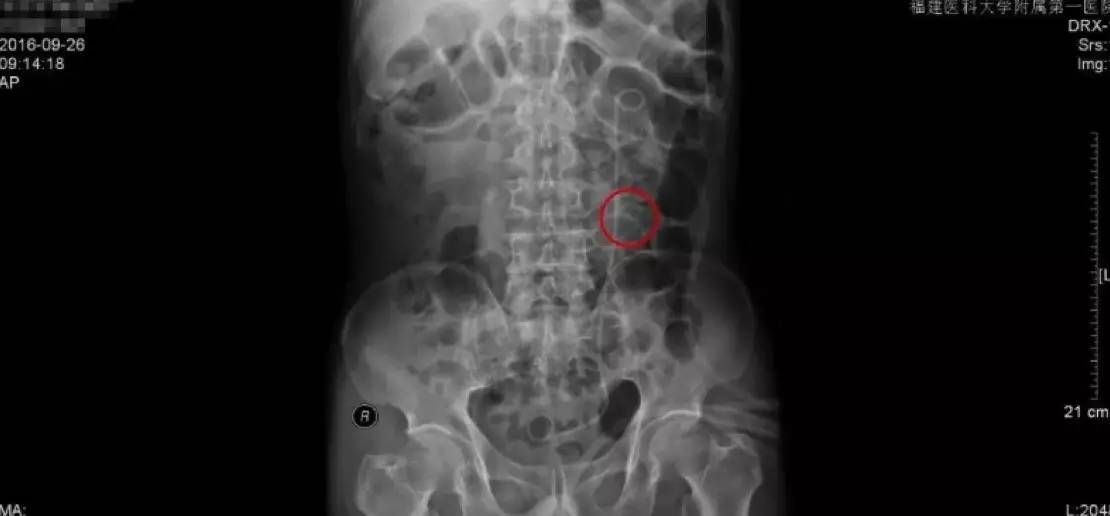

手术后的复查主要是通过拍KUB,通过与手术前KUB报告的直观对比,从图中能够看到,原来结石的地方,强化的结石已经消失了,左侧能够看到箭头指示的是一根手术后留置的双J管,这根管的目的是为了防止手术后输尿管狭窄黏连。

由于我们的手术是通过输尿管操作的,对输尿管粘膜不同程度有损伤,如果不留置双J管的话,术后容易造成输尿管黏连狭窄,输尿管最细的地方只有0.5cm,所以狭窄是手术后需要注意的并发症。